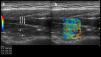

(a) Long-axis grayscale US image of the supraspinatus muscle belly. Central tendon (long arrows) and pennate pattern are visible. There is mildly increased echogenicity relative to normal background muscle (asterisks). (b) SWE image (color elastogram) of the same region shows predominantly intermediate shear-wave velocity on anterior (1), posterior (2) and myotendinous junction (3,1.94 m/sec, 2.52 m/sec, 2.12 m/sec, respectively). Red = hard consistency (7.1 m/sec), blue = soft consistency (0.0 m/sec), and green and yellow = intermediate consistency. SWE data were collected using a Logiq S8 R4 (General Electric, United States) with an L9–15-MHz linear transducer.